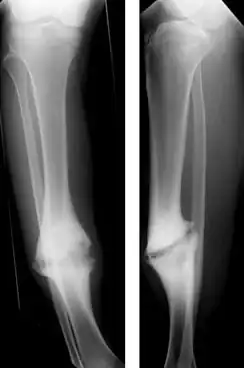

Hypertrophic nonunion of the tibia

Hypertrophic nonunion

In a hypertrophic nonunion, the fracture site contains adequate blood supply but the fracture ends fail to heal together.[6] X-rays show abundant callus formation. This type of nonunion is thought to occur when the body has adequate biology, such as stem cells and blood supply, but inadequate stability, meaning the bone ends are moving too much. Typically, the treatment consists of increasing stability of the fracture site with surgical implants.[7]